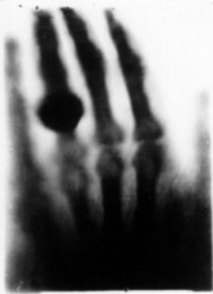

• Raigs X

Raigs X